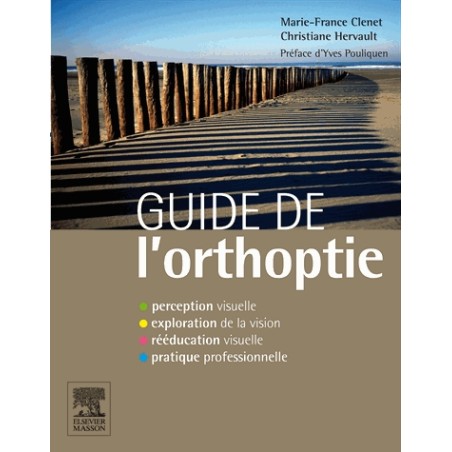

19,90 €

19,90 €Prix